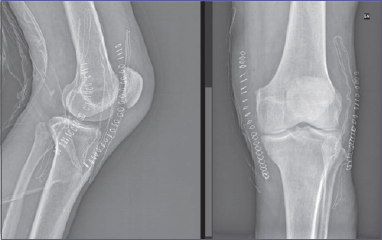

On inspection, the knee was swollen, an anatomical deformity with 90° knee flexion was noted. The patient did not complain of paresthesia or sensory deficits. The limb was warm and with palpable pulses. X-ray exam showed a PL knee dislocation (Fig. 1). Closed reduction and immobilization with posterior brace were performed, under conscious sedation, in the emergency department. Neurovascular status was closely monitored. Angio-CT scan was performed to exclude vascular injuries (Fig. 2). The patient was hospitalized. Neurovascular status, skin condition and clinical parameters were strictly monitored. The knee was unstable with persistent PL subluxation, worsened by dyskinesias, and both varus and valgus instability. The lesion was classified as a grade IV KD of Knee Dislocation Classification System. A staged multi-ligament reconstruction in two steps was planned: acute reparation of MCL and LCL and a staged reconstruction of both ACL and PCL. A neurologist was consulted to optimize the patient’s therapy with the aim of reducing the risk of recurrence. After 3 days we performed an acute surgical reparation of both the MCL and LCL. A 30° locked knee brace was placed. Postoperative X-rays exam (Fig. 3) showed perfect knee reduction. On the fifth postoperative day the patient was discharged with home care and an outpatient controls program. We planned to unlock the brace after 25 days, check the ligament status and then perform a knee MRI in order to plan an ACL-LCL reconstruction within 2 months. After 25 days, patient came to the outpatient department to unlock the brace. We noticed a relapse of PL subluxation with varus-valgus instability and failure of the MC and LCL reparation. The main causes of failure were the persistent and violent dyskinesias, due to Parkinson disease. In this context, plan a staged reconstruction would have been at high risk of another ligament failure. Thus, we talked with patient, and changed the strategy. Three months after the injury the patient was hospitalized and underwent, in general anesthesia, a total knee replacement with a hinged prosthesis (Fig. 4). We choose a hinged prosthesis to make the implant as stable as possible to resist dyskinesias. Postoperative anemia was observed, requiring the transfusion of 2 concentrated red blood cell units. No other postoperative complication was observed. From the day after surgery the patient started active and passive mobilization of the knee and a re-education protocol with full weight bearing. The patient was discharged on the 7th postoperative day to continue rehabilitation. Clinical and radiographic controls were performed at 3, 6, 12 months and then annual follow-up. At the last follow-up (3 years) the patient was walking without crutches, with full ROM, no pain and the same level of activity as before the injury (Fig. 5).

Figure 3.Postoperative X-Ray after MCL and LCL reparation.